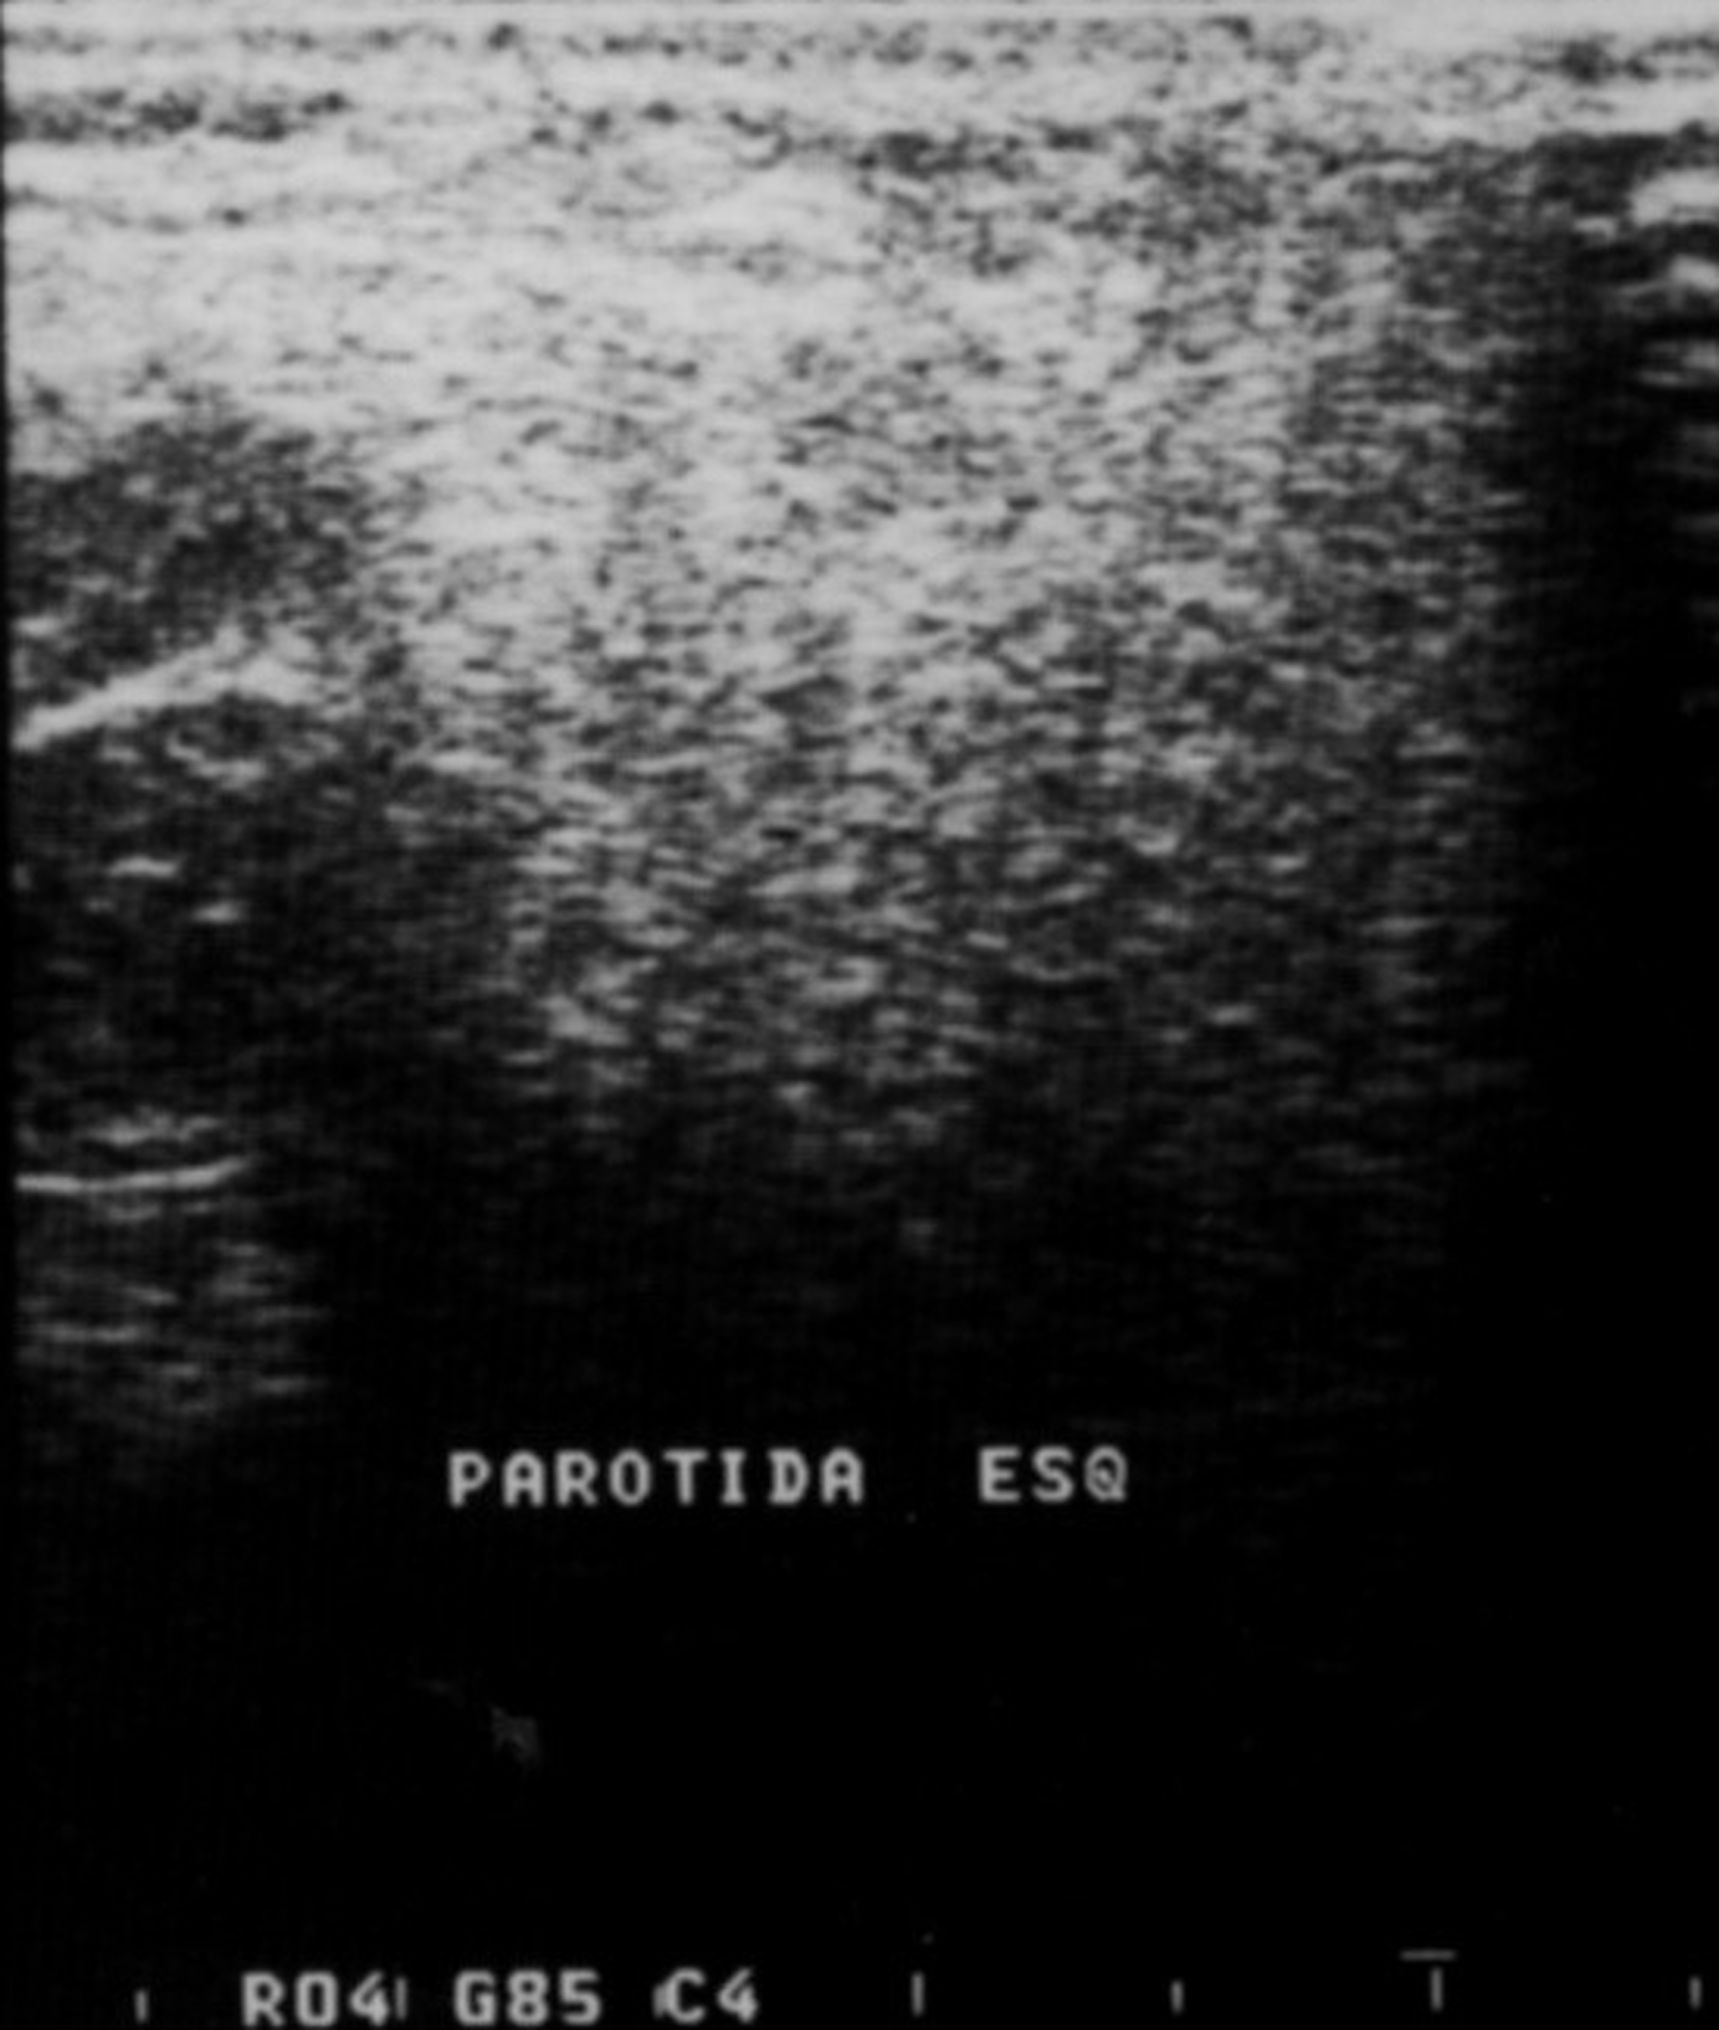

Fig 3. Sonogram of the left parotid gland showing normal pattern.

Figure 3

Imaging analyses, including ultrasonography and sialography, of the parotid glands were performed. Ultrasonographic features of the cervical region did not show any alterations of the submandibular and left parotid glands (Figure 2 through Figure 5). However, the right parotid gland demonstrated an inhomogeneous structure of the gland with scattered, multiple, small, oval, hypoechoic, or anechoic areas, usually well defined, and increased parenchymal blood flow. Sialographic examination of the right parotid gland showed a snowflake-like form and Christmas-tree pattern and evidence of sialoangiectasia without any changes of duct anatomy (Figure 6). Even after the salivary stimulation, the duct system was kept filled by the contrast fluid that again highlighted the sialectatic changes (Figure 7).